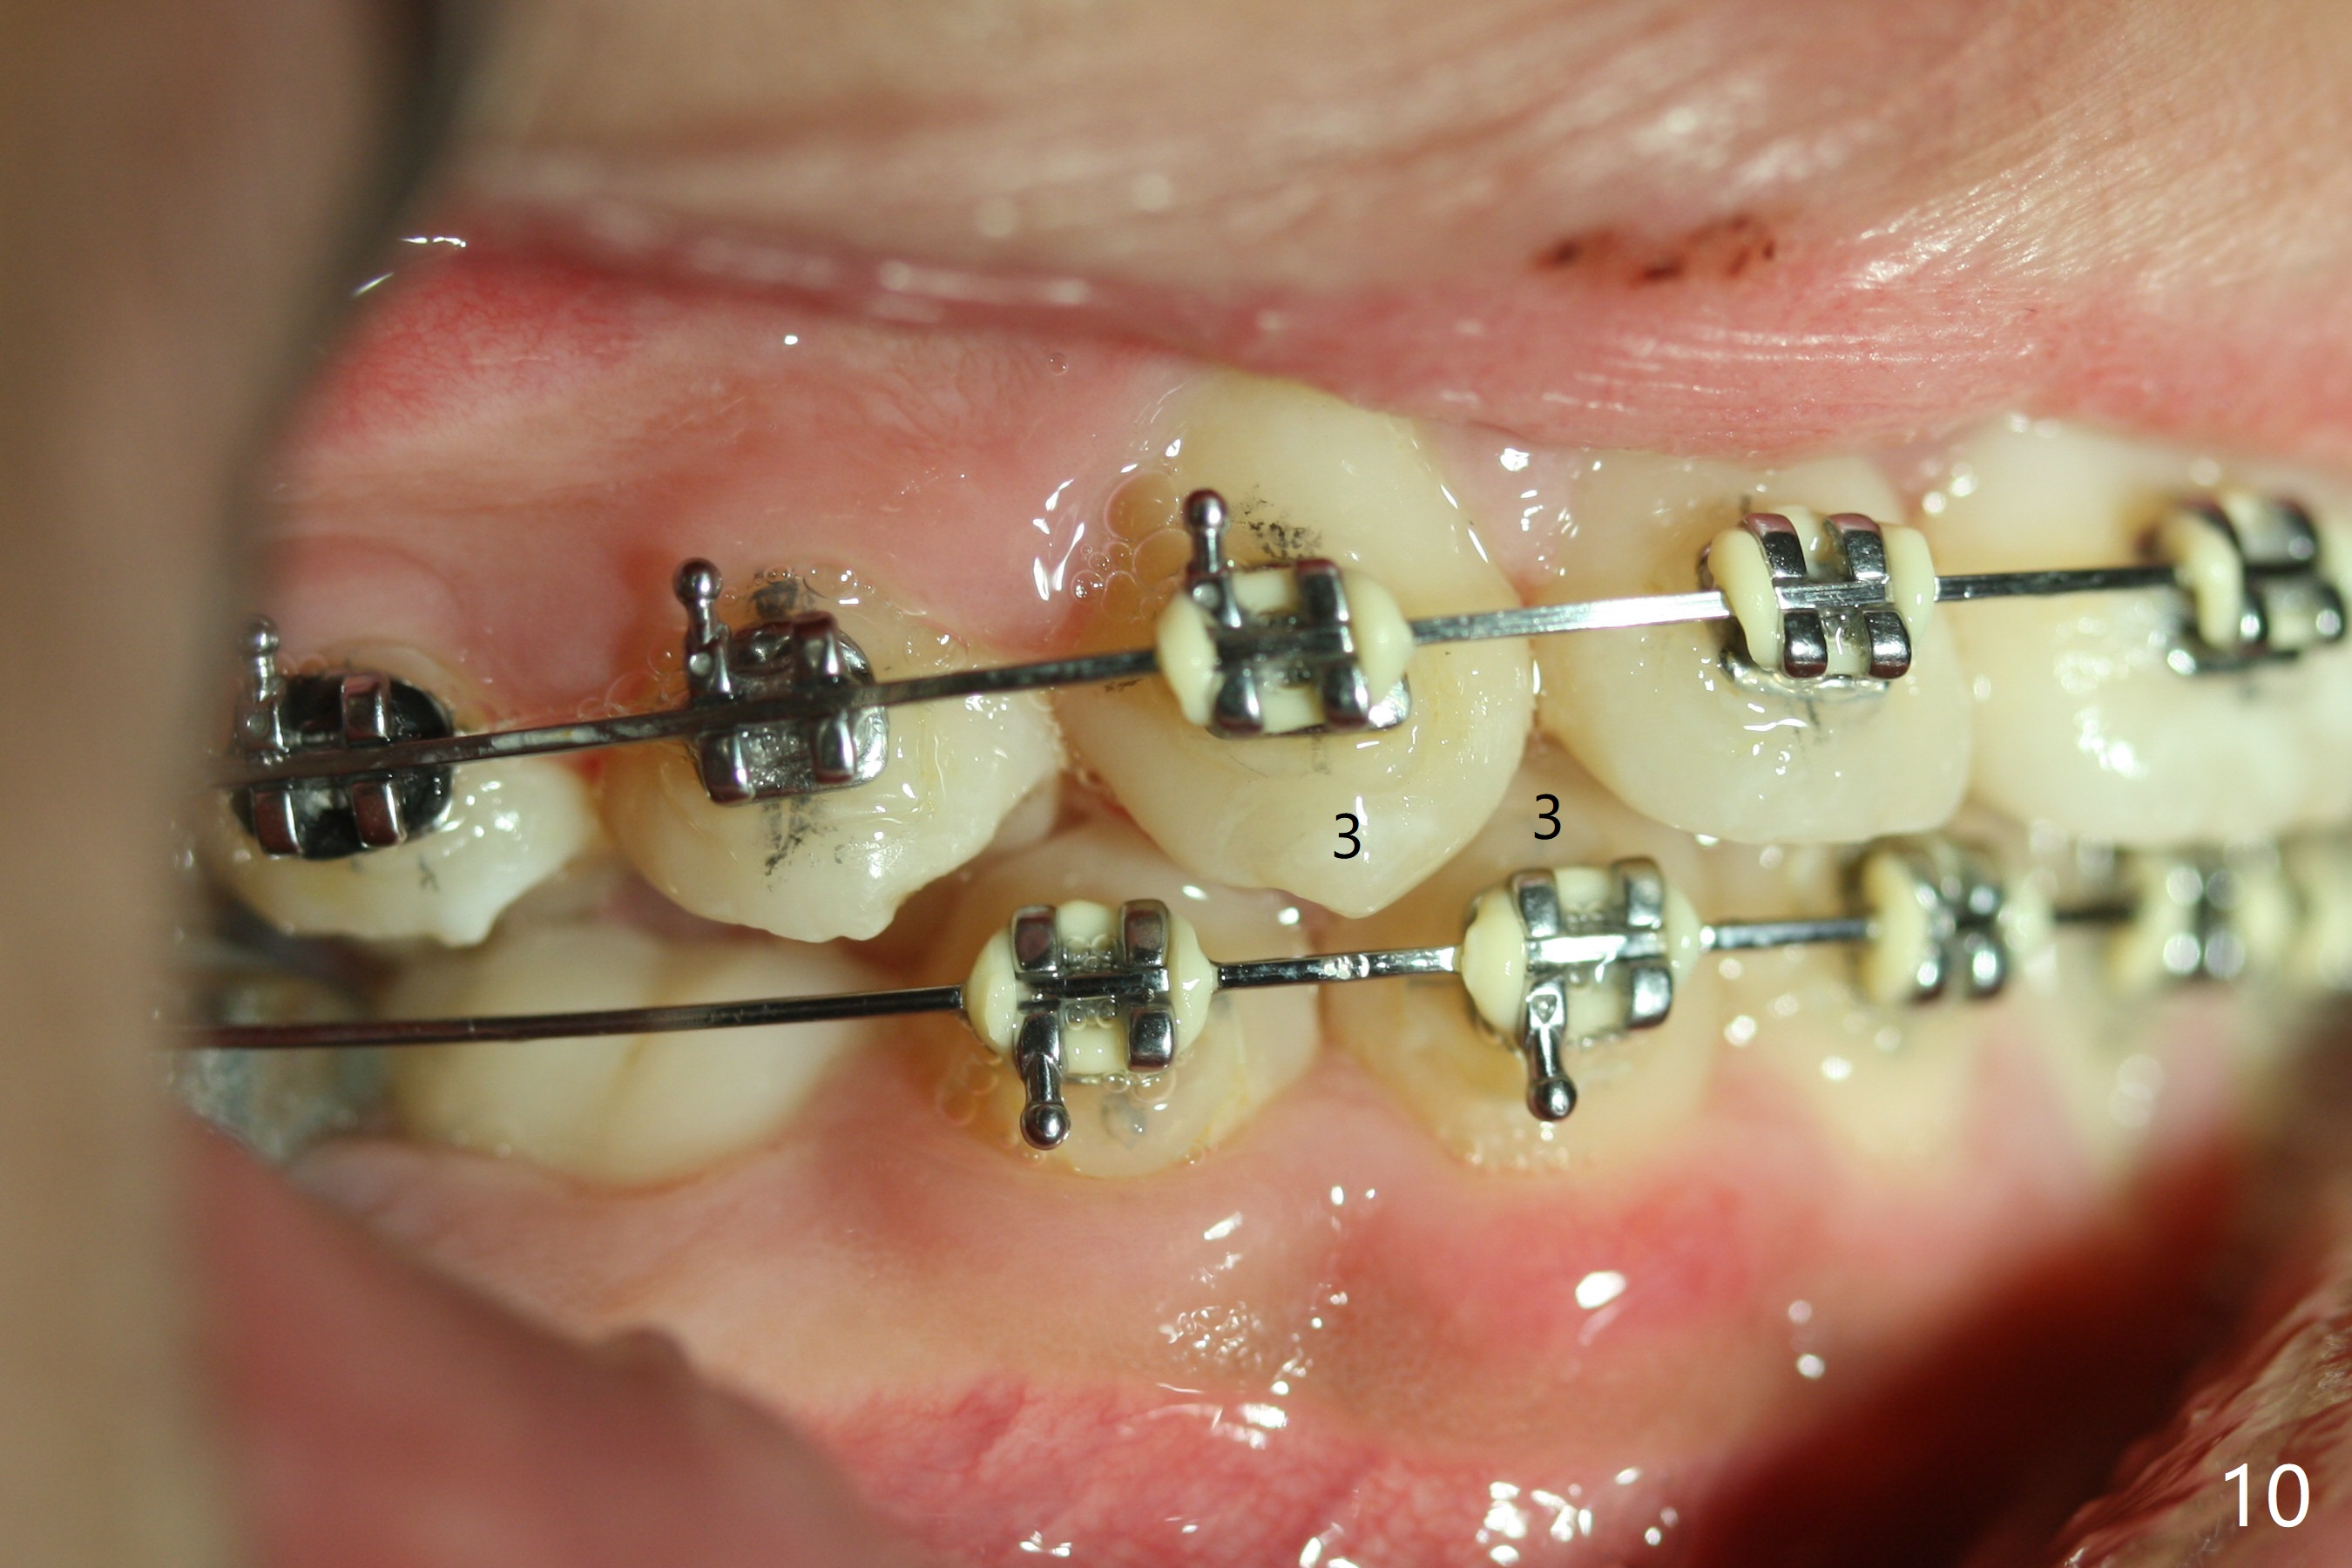

Eight months post banding, the interdigitation on the right side seems to be within normal limit (Fig.10), while the lower dental midline appears to be deviated to the left (Fig.11) with anterior overjet (Fig.12). The left canines remain Class II; open coil spring is placed between LL3-6 with intention to reduce anterior overjet and correct the lower midline deviation (Fig.13). Four weeks later, LL3 does not seem to be mesialized. It appears that the long open coil spring between LL3-6 is not effective. A molar band is added to LL E (Fig. 14,15). When a molar band is placed in LL7, an upper niti wire will be placed in the lower arch to expand the arch. When arch wire turns into thicker one, place open coil spring between LL3 and E.